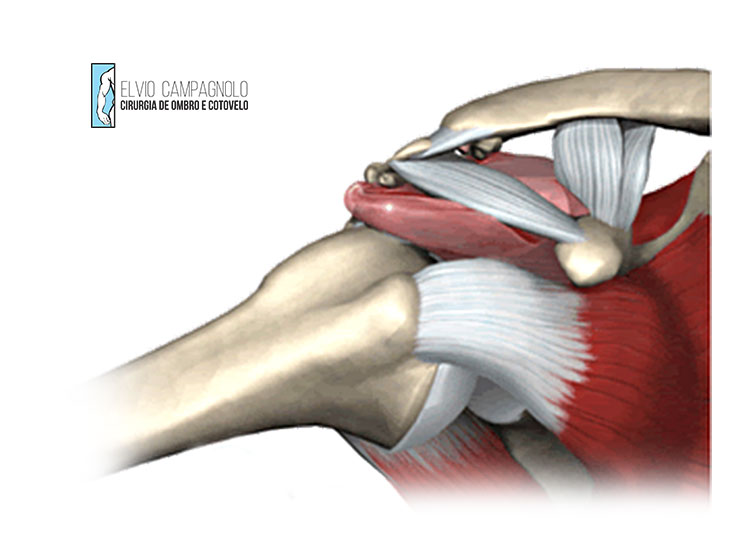

As lesões do manguito rotador envolvem rupturas parciais ou totais dos tendões responsáveis por manter a estabilidade e o movimento do ombro. Essas estruturas são fundamentais para atividades cotidianas, como levantar o braço, alcançar objetos ou vestir uma roupa. As causas mais comuns incluem esforço repetitivo, envelhecimento natural dos tendões ou traumas diretos.

O tratamento depende da extensão da lesão e do perfil do paciente. Em casos leves ou moderados, são indicados fisioterapia, fortalecimento muscular, medicamentos anti-inflamatórios e infiltrações guiadas por ultrassom para controle da dor. Em rupturas mais extensas ou em pacientes com limitação funcional importante, o tratamento cirúrgico — geralmente por via artroscópica — é o mais recomendado, permitindo a reparação dos tendões com mínima agressão aos tecidos e recuperação mais rápida.

A síndrome do impacto ocorre quando há compressão dos tendões do manguito rotador e da bursa subacromial entre o úmero e o acrômio durante o movimento do braço. Essa condição é comum em pessoas que realizam movimentos repetitivos acima da cabeça, como atletas de natação, vôlei e trabalhadores manuais.

O tratamento inicial é não cirúrgico, com fisioterapia para fortalecer o manguito rotador e melhorar o posicionamento da escápula. Podem ser usadas infiltrações guiadas por ultrassom e medicações anti-inflamatórias para alívio da dor. Quando há falha no tratamento clínico ou lesões associadas, pode ser indicada a artroscopia do ombro para remoção de tecido inflamado e correção do espaço subacromial.